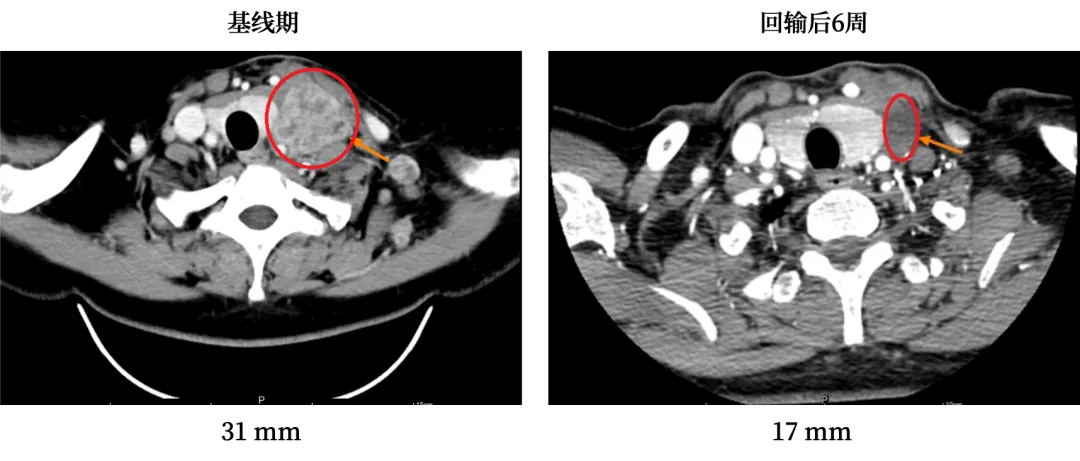

第二位是KRAS G12D突变的IVB期肺腺癌患者,2022年4月因左胸疼痛确诊,KRAS

G12D突变至今无上市靶向药可用。他先后接受免疫+化疗联合治疗、免疫+抗血管生成+化疗联合治疗,但因无法耐受药物不良反应被迫停药,病情迅速恶化,癌痛剧烈,生活无法自理。

入组GC101

TIL临床试验后,他接受了单次细胞回输,仅出现短暂的一过性血象降低。42天疗效评估时,肿瘤缩小45%,癌胚抗原恢复正常,颈部肿大的淋巴结彻底消失,癌痛也随之缓解,重新燃起了活下去的希望。